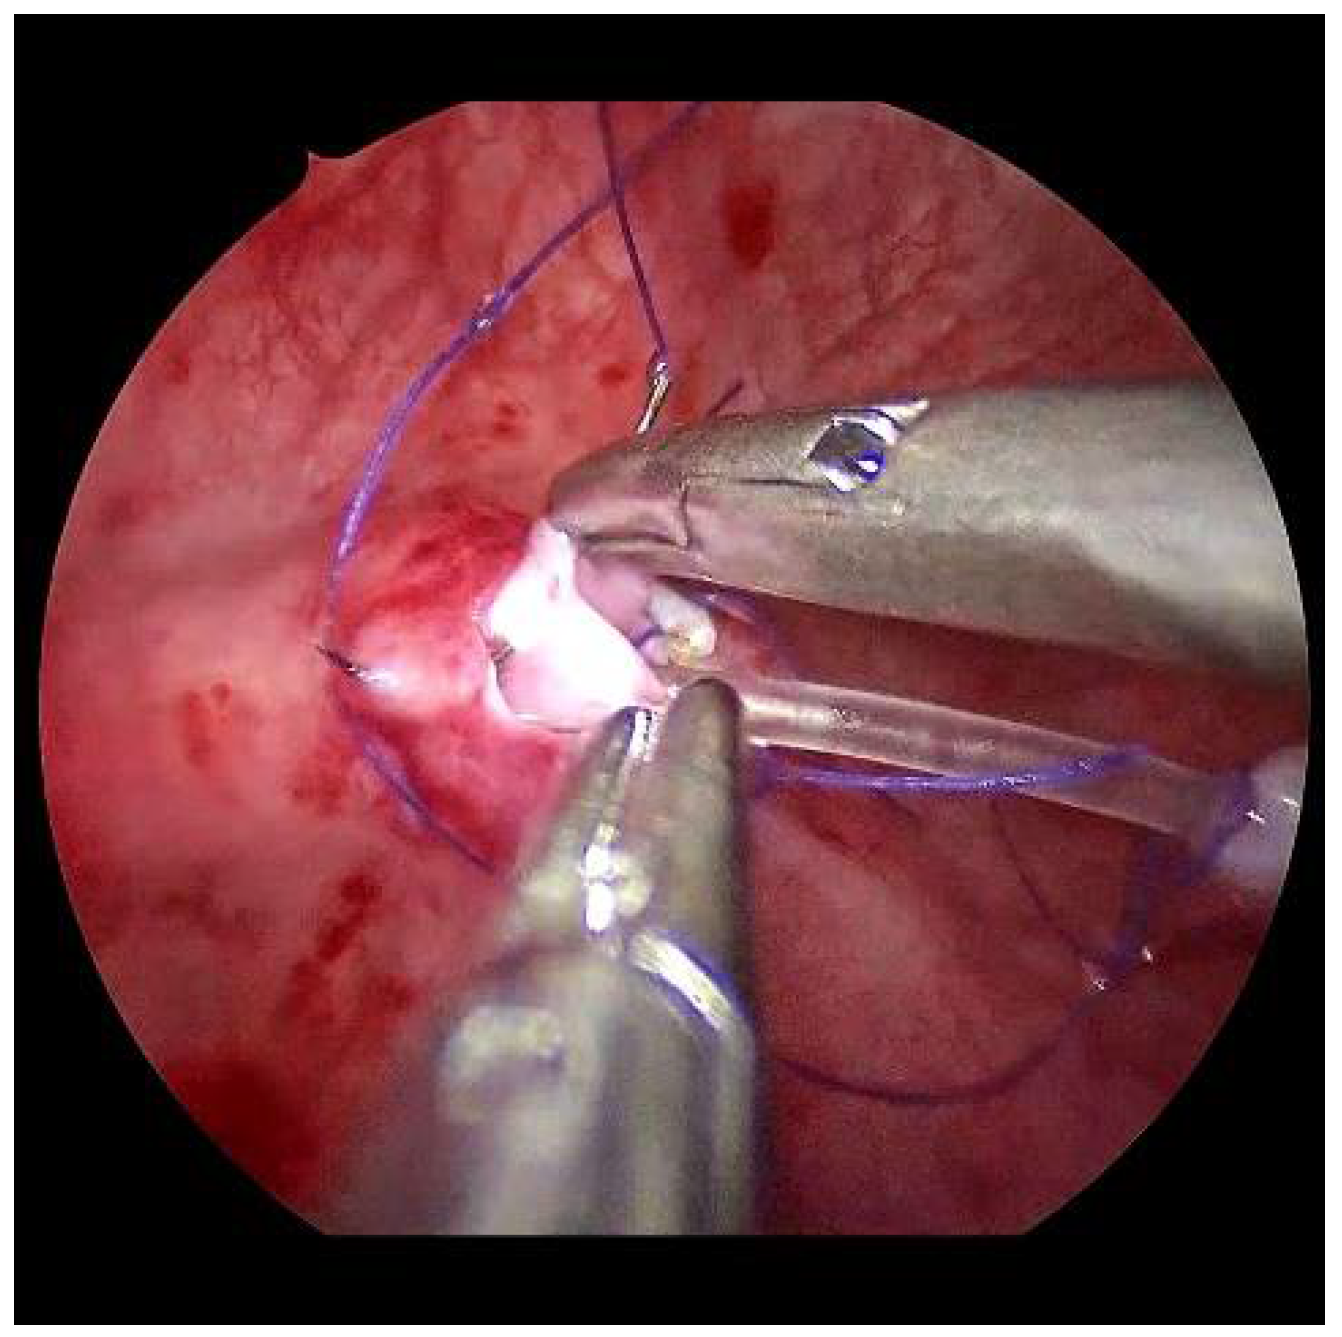

Submucosal tunnel preparation using curved scissors often requires some patience. When the tunnel is finished, the refluxive ureters are now shifted to the opposite side equivalent to the open approach. An ipsilateral suture fixes the ureter to the detrusor (Figure 6).

Figure 5. The submucosal tunnel is subtly prepared with curved scissors.